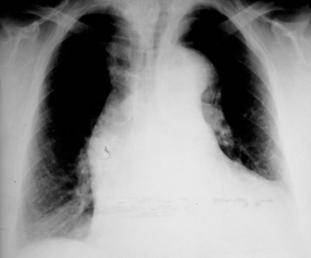

Figura 37. La radiografía portátil AP de tórax (imagen A y ampliada en la imagen B) revela fracturas agudas de las caras laterales de las costillas 2, 3 y 4 del lado izquierdo (flechas rojas) después de un traumatismo.